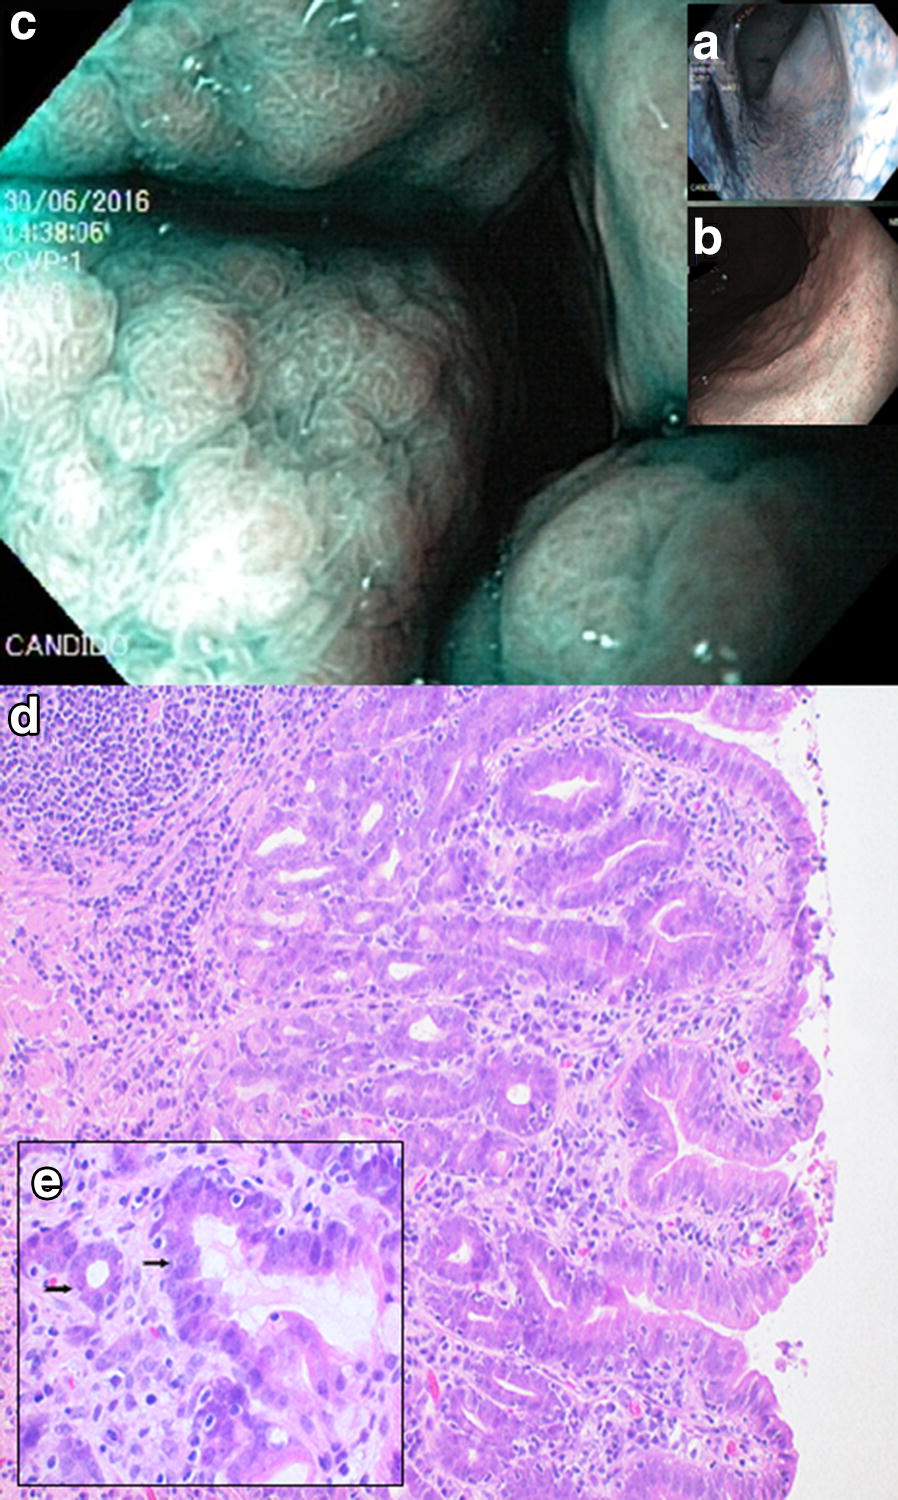

Fig. 7.

Endoscopic and corresponding histologic images of a 9-year-old female Belgian Tervuren showing dysplasia. Endoscopic images (a, b, c) show diffuse mucosal texture irregularity along gastric fundus and body: a chromoendoscopy (CE), b narrow band imaging (NBI), c CE and NBI combined. Histology: d dysplasia of the fundic glands, with glandular dilatation and distortion. e Cellular dysplasia with flattening of the glandular cells and loss of cellular polarity (arrows). HE stain, d Obj. 20×, e Obj. 40×

The final diagnosis considered for all of the analyses was achieved by endoscopic examination and sampling, followed by histopathological confirmation. All dogs presenting the changes of concern were also found with concomitant inflammatory changes (Table 3). Each set of sample images shown in this article correspond to a single patient, respectively diagnosed as carcinoma (Figs. 4, 5), metaplasia (Fig. 6) or dysplasia (Fig. 7). Chromoendoscopy and narrow band imaging were applied in one Belgian Tervuren presented with chronic vomiting, whose brother from the same litter had been euthanized due to a massive GC. The most prominent endoscopic and respective histopathological changes found in this patient are in Fig. 7.

Gastric metaplasia or dysplasia were almost as rarely seen as GC, with significantly higher relative risks found for the Belgian Tervuren and Shetland Sheepdog. Although statistical significance could not be confirmed for every breed, both types of changes were found in Belgian Tervuren, Collie and Golden Retriever, sometimes in the same patient. Nonetheless, metaplasia and dysplasia can present as discrete, flat changes that are easily overlooked and possibly underdiagnosed [24], especially when considering the limitations of current white light endoscopy modalities available and non-directed sampling procedures in veterinary medicine. Visual enhancement techniques such as chromoendoscopy and narrow band imaging (Fig. 7) may help improve the diagnostic yield of discrete mucosal changes [9].

The diagnosis of metaplastic or dysplastic changes in breeds with predispositions to GC might indicate a stepwise progression in dogs, comparable to the better known pathway towards GC in humans [10]. Studies in Lundehund dogs with GC ponder on a similar pathogenesis [17, 18]. This might be the case especially for the Belgian Tervuren with its significantly higher relative risk for the suspected pre-neoplastic changes, along with its marked predisposition for GC. This hypothesis might be further explored by staging suspected lesions and screening dogs selected from predisposed breeds. Research should aim at applying more advanced endoscopic approaches such as chromoendoscopy or narrow band imaging, which are proven modalities in humans for improving the targeted sampling of lesions [29] that might be easily overlooked when using white light endoscopy alone. Metaplasia and dysplasia have not been consistently studied in canine gastroenterology and their potentially relevant role in the pathogenesis of canine GC must be further investigated, whereas in humans well-established staging protocols and advanced therapeutic approaches are routinely applied [30]. While standard guidelines for histopathology evaluation remain fluid in veterinary medicine, novel immune staining techniques and genetic examination of biopsy samples may provide valuable opportunities for both research and diagnosis in the near future [31].